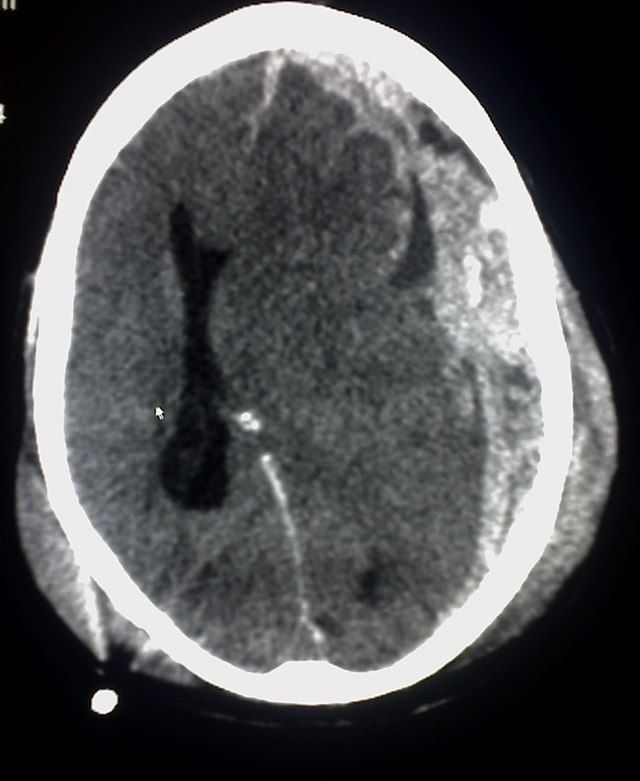

Interpret a CT head of an acutely unwell patient

Your consultant asks you to talk through the CT head which has just been completed.

Please answer all of the questions which he has for you.